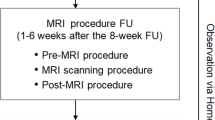

The procedural workflow for SBRT is shown in Fig. 1. During the planning phase of the procedure, 3D electroanatomic maps were exported from the mapping system (CARTO-3; Biosense Webster, Diamond Bar, CA, USA) to a notebook with a viewer software. All patients underwent either electrocardiography (ECG)-gated delayed-enhancement magnetic resonance imaging (DE-MRI) or dual-energy CT to identify the scar regions. The CT/MRI images were visually compared with 3D electroanatomic maps, which showed the targets of SBRT. A contoured target volume was jointly created by the electrophysiologist, cardiac radiologist, and radiation oncologist. After an SBRT simulation, irradiation was performed and overseen by the radiation oncologist. The patients were hospitalized on the day of radiation treatment and discharged on the next day, in the absence of any immediate complication.

After radiation therapy, the patients visited the outpatient clinic at weeks 1 and 4 after radioablation, and every 1 month for unstable patients and every 3 months for relatively stable patients thereafter. Chest radiography and transthoracic echocardiography were performed to evaluate for possible complications, including pericardial effusion or radiation pneumonitis. Post-radiation MRI or CT evaluations were performed in eligible patients. ICD interrogation was performed at the electrophysiologist visit. For patients with PVCs, 24-h Holter monitoring was performed to assess the radiation efficacy. Anti-arrhythmic medications were titrated by an electrophysiologist according to each patient’s clinical condition.